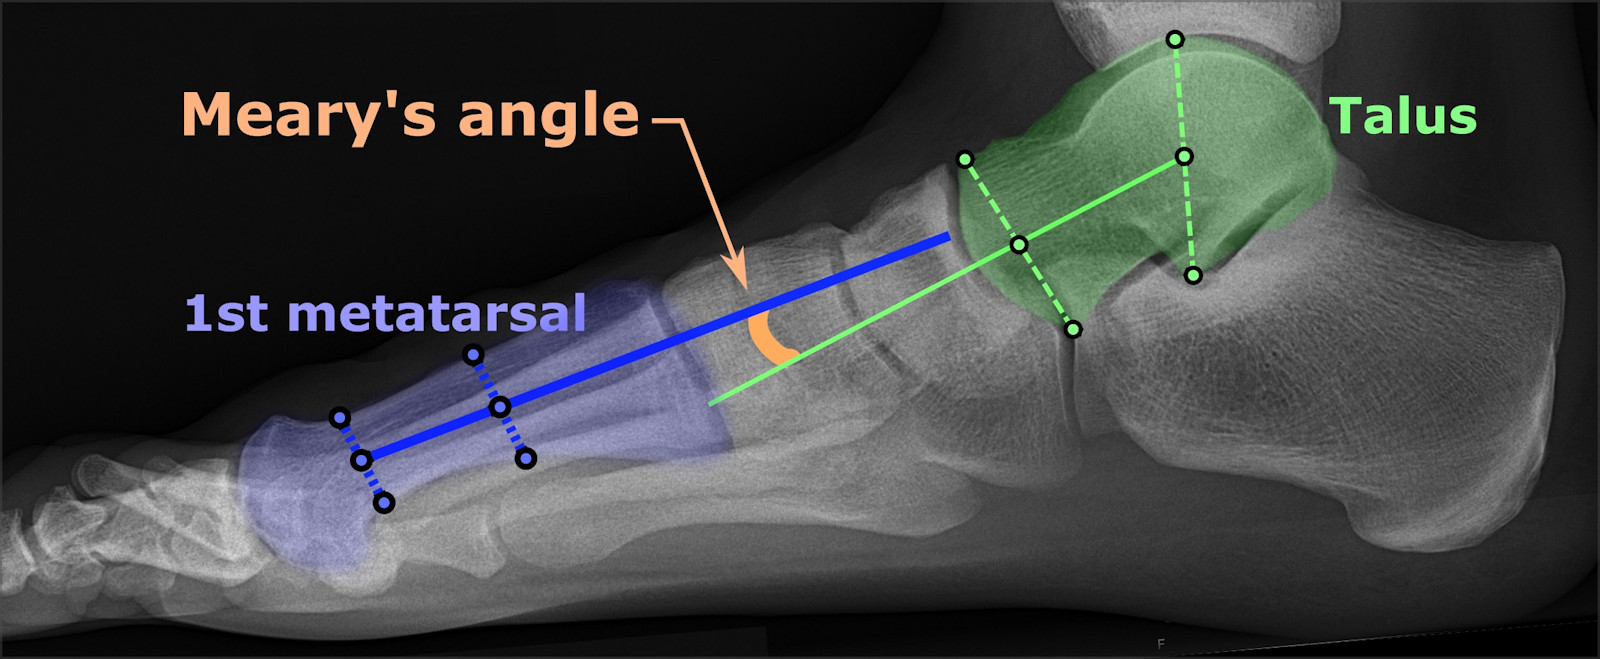

Radiologisch als een denkbeeldige as die door het midden van de talus wordt

getrokken, loodrecht op het gewrichtsvlak, niet uitkomt in het midden van het

eerste metatarsale bot van dig I. Normaal als de botten netjes in elkaars verlengde

staan hoort men een rechte lijn te kunnen trekken door metatarsale 1 en de tarsus.

platvoet |